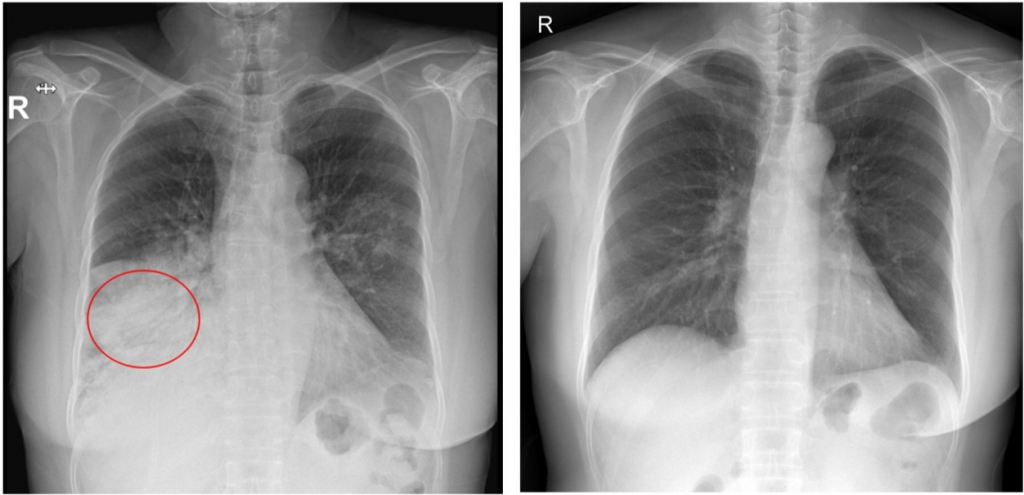

폐렴은 세균·바이러스가 폐로 침투해 염증이 생긴 병이다. 폐렴구균으로 인한 '세균성 폐렴'이 흔하다. 가톨릭대 서울성모병원 호흡기내과 민진수 교수는 "폐렴구균은 평소에도 코·목의 점막에 상주한다"면서도 "우리 몸의 면역력이 약해지면 폐렴구균이 폐·뇌·혈관·귀까지 침투해 폐렴·수막염 등을 일으킨다"고 설명했다.

폐렴의 초기 증상은 발열·기침·가래 등 일반 감기와 비슷하다. 하지만 폐렴구균이 본격적으로 활동하기 시작하면 고열·기침·가슴 통증·호흡곤란을 유발한다. 숨이 가빠지면 호흡수도 많아져 1분당 20회를 초과하는 게 특징이다.

폐렴구균으로 인한 폐렴일 경우 가래 색깔이 '적갈색'으로 진하게 바뀌기도 한다. 폐렴으로 인해 폐가 망가지면 폐의 산소 교환 기능이 떨어지고, 이에 따라 핏속 산소 농도가 떨어진다. 입술이 파랗게 변하는 '청색증'이 폐렴 합병증의 증상인 이유다. 민진수 교수는 "이 정도가 되면 생명이 위험할 수 있으므로 반드시 병원을 찾아야 한다"고 경고했다.